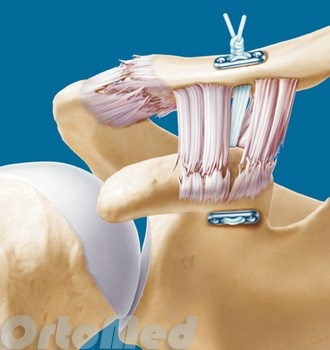

Tratamentul chirurgical implică eliminarea de deformări osoase severe. Aceasta poate necesita o intervenție chirurgicală pentru a elimina sfârșitul claviculei, de recuperare a ligamentelor.